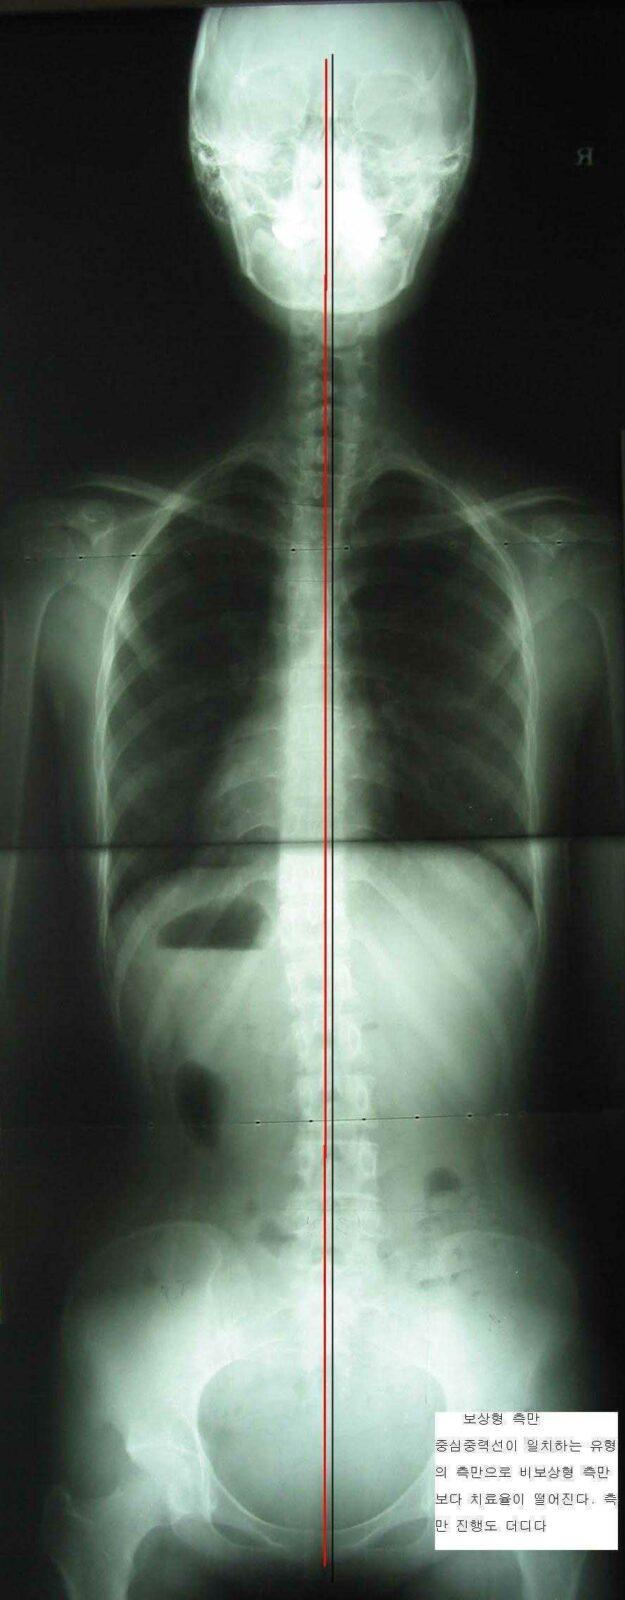

척추 측만증이 생겨 척추가 옆으로 휘게 되면 우리 몸의 중심 (균형)을 잃게 되는데 이 균형을 잡으려고 척추는 반대 방향으로 휘어서 균형을 잡으려고 합니다. 이를 보상이라고 하는데 성장기에는 이 보상작용이 계속 이루어지지만 사춘기 이후에는 대개 보상작용이 종료됩니다. 보상작용이 끝나기 전에는 치료 결과가 좋지만 보상이 끝난 후에는 치료 결과가 현저하게 감소됩니다.

- 사춘기 이후에는 척추의 보상이 끝나버려 척추 측만증의 치료율이 현저히 감소됩니다.